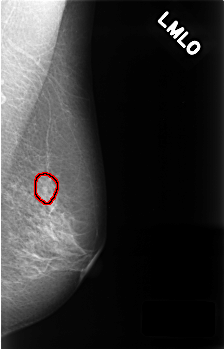

C_0406_1.LEFT_MLO

LEFT_MLO LINES 4528 PIXELS_PER_LINE 2904 BITS_PER_PIXEL 12 RESOLUTION 50 OVERLAY

FILE: C_0406_1.LEFT_MLO.OVERLAY

TOTAL_ABNORMALITIES 1

ABNORMALITY 1

LESION_TYPE CALCIFICATION TYPE AMORPHOUS DISTRIBUTION CLUSTERED

ASSESSMENT 4

SUBTLETY 2

PATHOLOGY BENIGN

TOTAL_OUTLINES 1

BOUNDARY